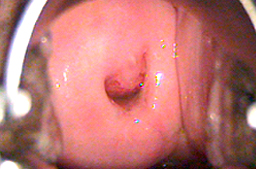

Lesiones en Cérvix

NIC 2 o Displasia moderada asociada a infección por VPH

Neoplasia Intraepitelial de Cérvix grado 2 o Displasia moderada.